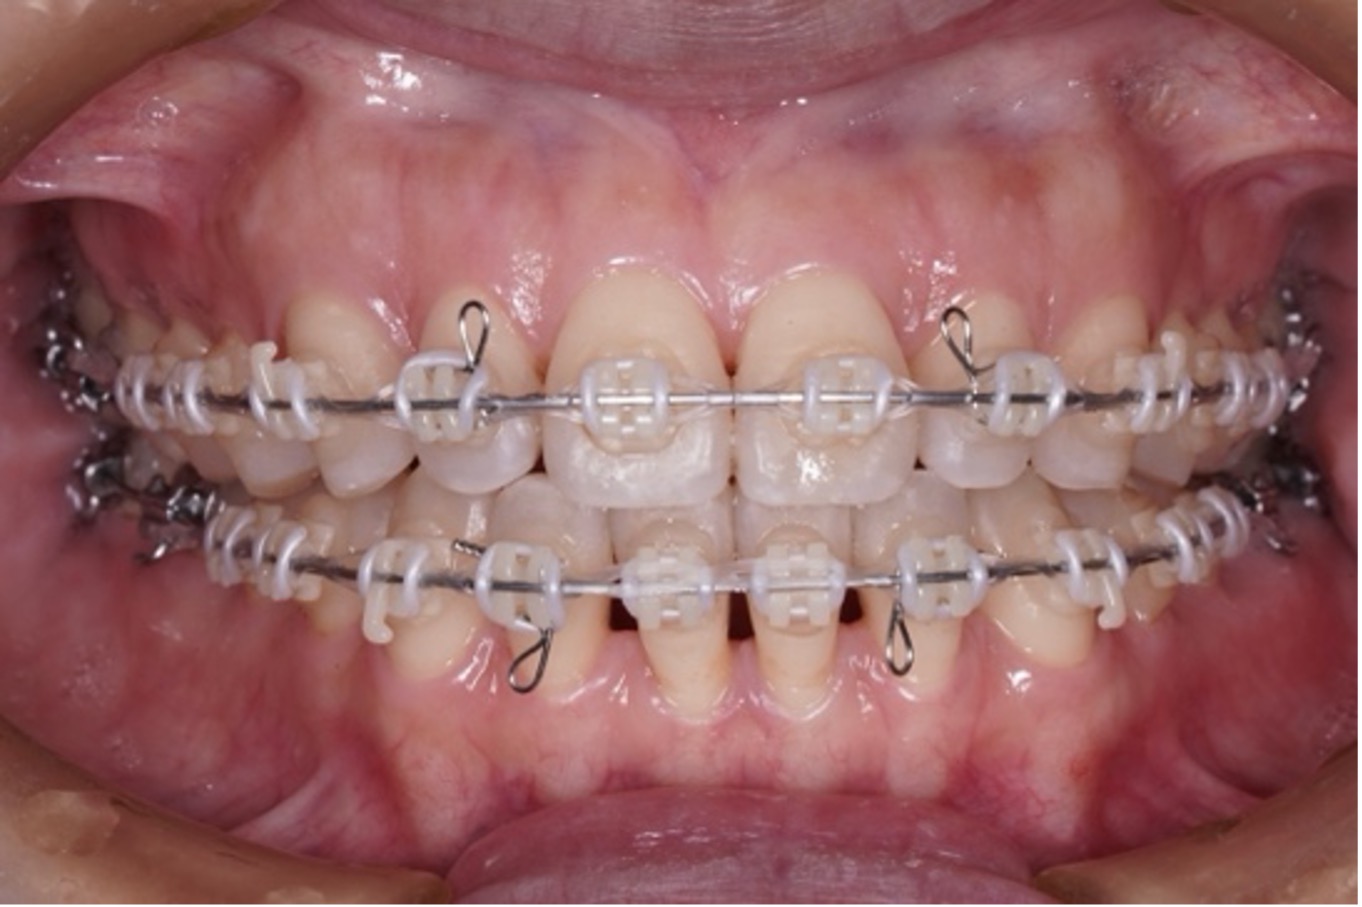

歯の表面または裏側にブラケットを装着し、ワイヤーの力で歯を動かす伝統的な方法です。

現在も多くの矯正歯科で採用されており、精密で確実な歯の移動が可能です。

近年は、「ワイヤーで歯の土台を整え、マウスピースで最終調整を行う」ハイブリッド矯正が人気を集めています。

⚫︎見た目・精度・期間のバランスが良い

⚫︎症例に合わせて柔軟に対応可能